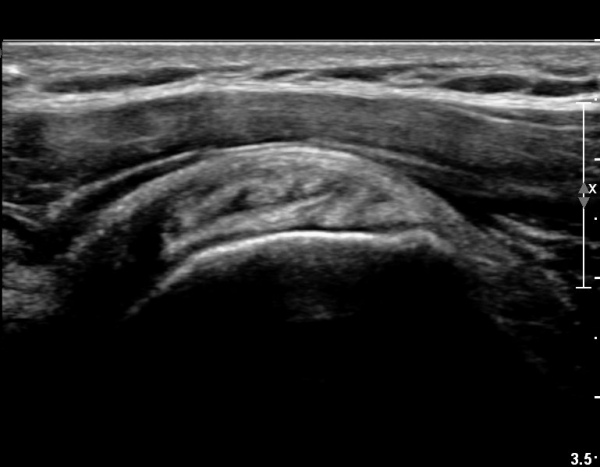

ÃÊÀ½ÆÄ ¼Ò°ß :  ȸÀü±Ù°³ °í¶û  °Ë»ç¸¦ À§ÇÑ »ó¿Ï Á߸³À§¿¡¼­ °ß°©ÇÏ±Ù°Ç °Ë»ç¸¦ À§ÇØ  ŽÃËÀÚ¸¦

¾à°£ ³»ÃøÀ¸·Î ±â¿ï¿© ½ÃÇàÇÑ °ß°©ÇÏ±Ù°Ç Á¾´Ü¸é°Ë»ç¿¡¼­ °ß°©ÇÏ±Ù°Ç »óºÎ°ÇÀÇ

Á¾¹æÇ⠺и®(½ÇÁú³» ÆÄ¿­)°¡ °üÂûµÈ´Ù(»çÁø 1).